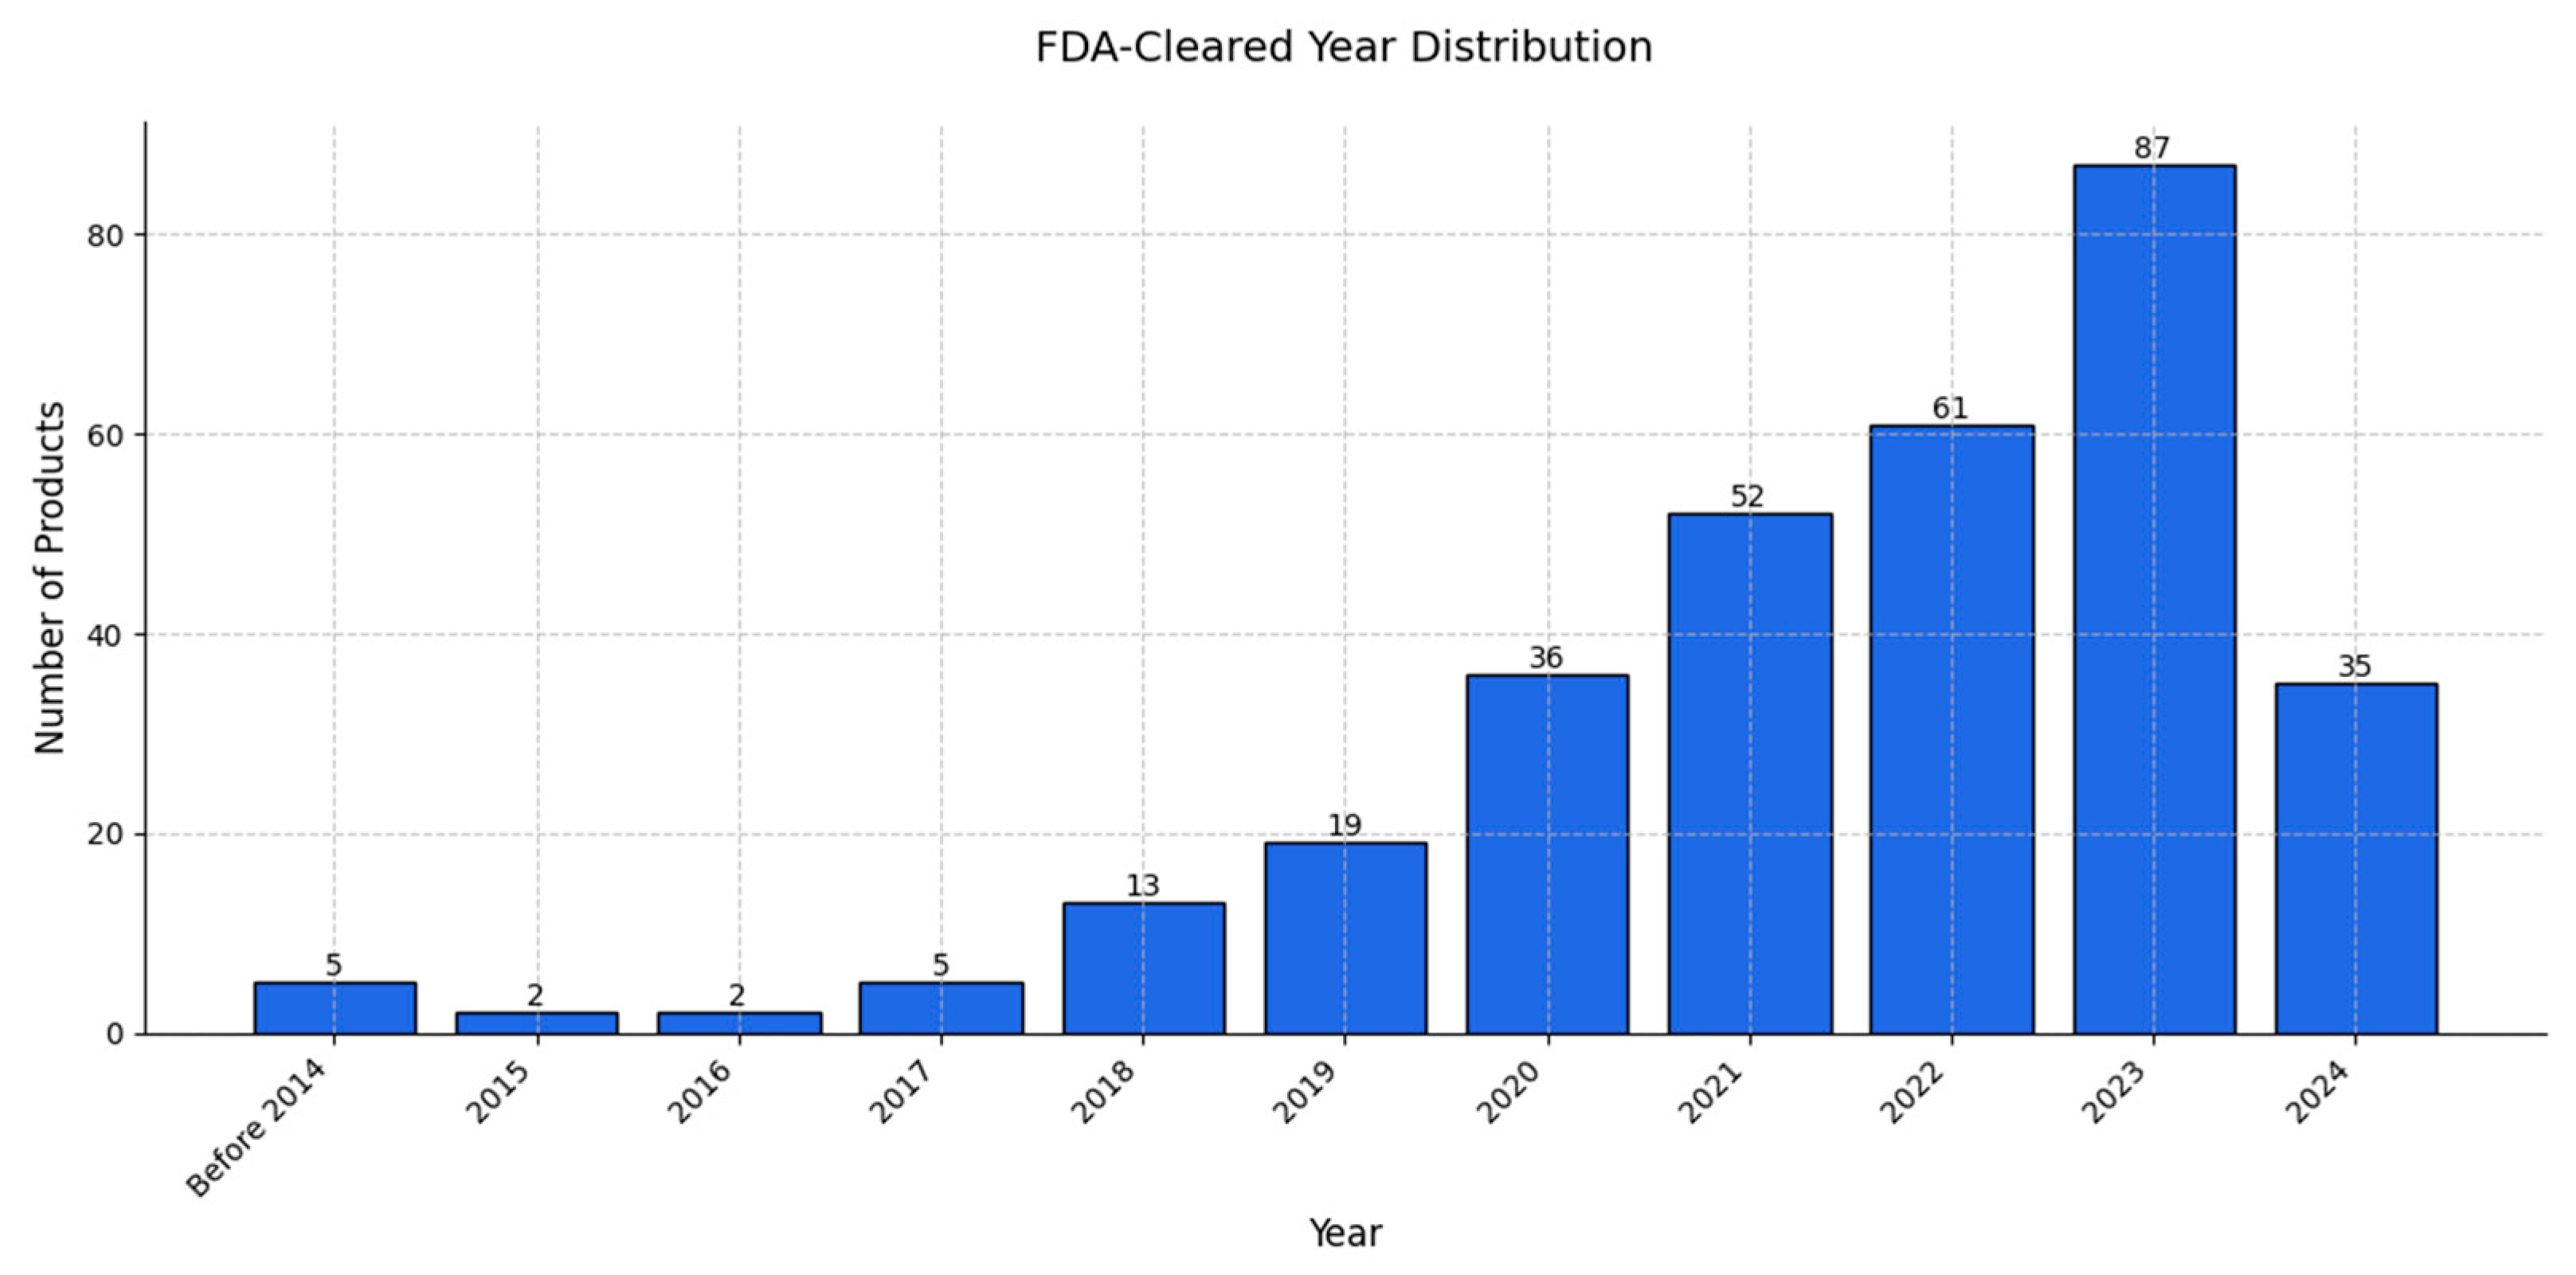

9. Review of AI Products Used in Radiology: Status in 2024

- Fornell, D. FDA Has Now Cleared 700 AI Healthcare Algorithms, More Than 76% in Radiology. Health Imaging. 2023. Available online: https://healthimaging.com/topics/artificial-intelligence/fda-has-now-cleared-700-ai-healthcare-algorithms-more-76-radiology (accessed on 1 December 2024).

- Zhu, S.; Gilbert, M.; Chetty, I.; Siddiqui, F. The 2021 Landscape of FDA-Approved Artificial Intelligence/Machine Learning-Enabled Medical Devices: An Analysis of the Characteristics and Intended Use. Int. J. Med. Inform. 2022, 165, 104828. [Google Scholar] [CrossRef] [PubMed]